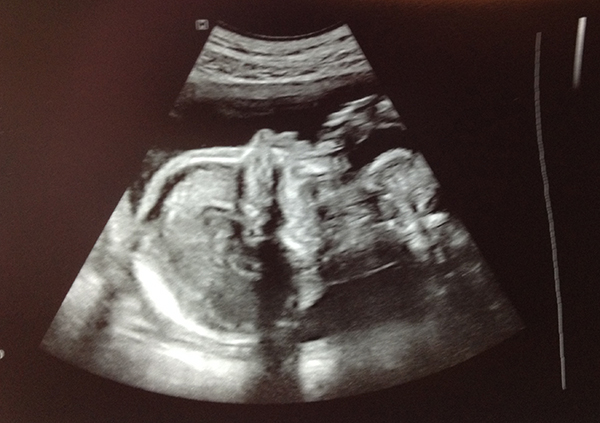

Wenig später liege ich parat und sehe am Monitor das Köpfchen meines Kindes. Dann können wir das Herz schlagen hören! Boa. Irre. Millionen Frauen sind jedes Jahr schwanger.

Aber bist du eine davon, dann ist irgendwie alles total spannend. JEDES DETAIL. Überwältigend. Faszinierend.

Also heute dann mal einen ersten Gruß von der kleinen Prinzessin, die gerade in meinem Bauch heran wächst.